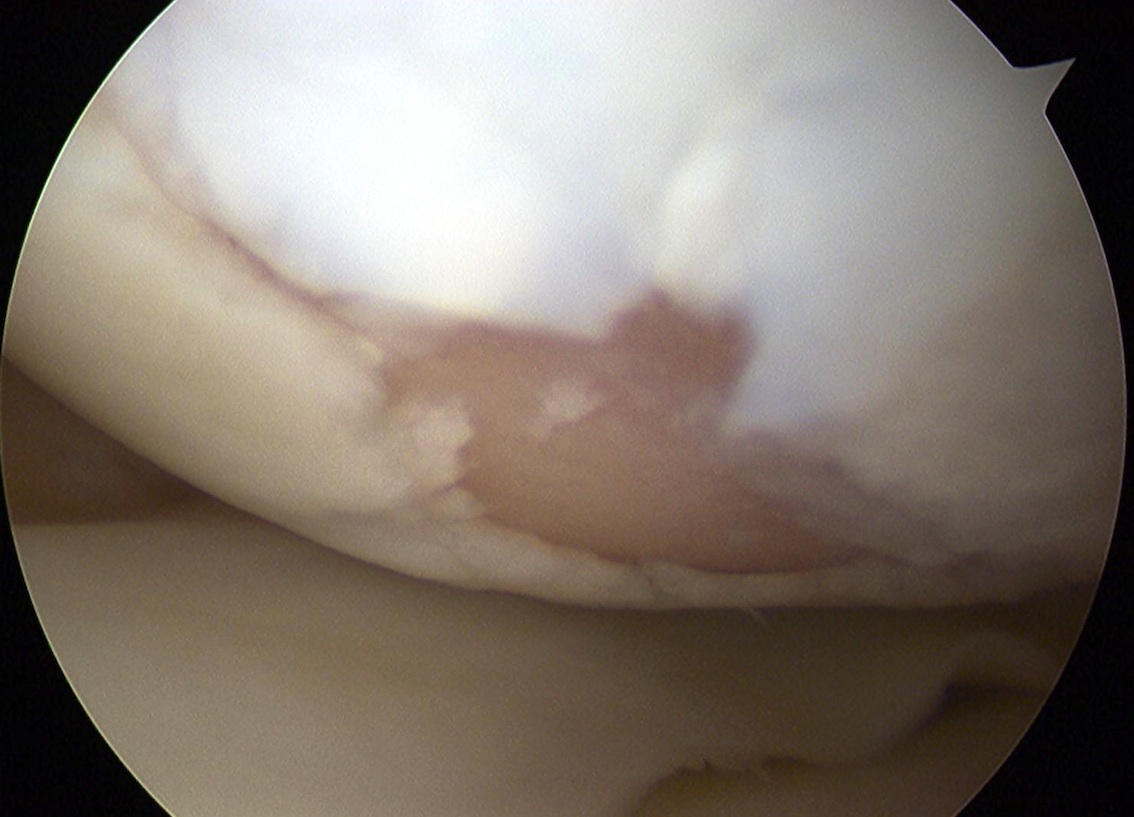

Cartilage defects

• Cartilage defects